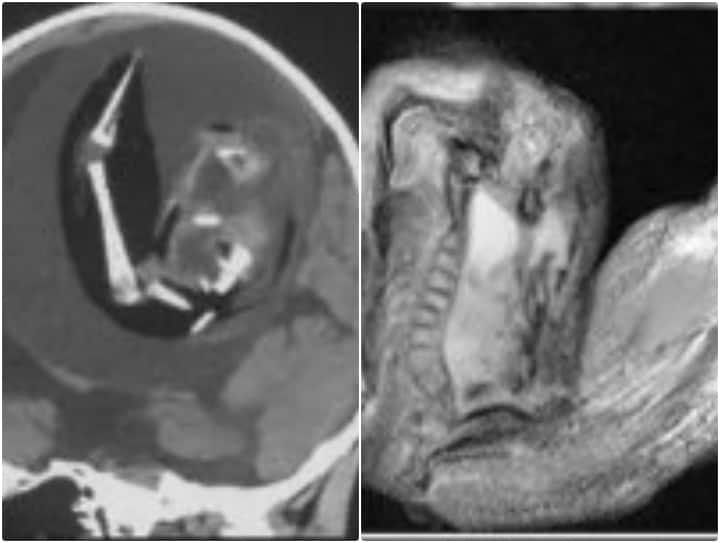

चीन में न्यूरोलॉजी जर्नल में प्रकाशित एक खबर के मुताबिक बताया गया है कि चीन में एक साल पहले पैदा होने वाली बच्ची के दिमाग के अंदर से एक भ्रूण को निकाला गया है. बताया जा रहा है कि जन्म लेने के बाद बच्ची के दिमाग का साइज काफी तेजी से बढ़ रहा था. जिससे परेशान उसके माता-पिता उसे इलाज के लिए अस्पताल लेकर पहुंचे. जहां उस बच्ची के दिमाग का सिटी स्कैन किया गया तो इस राज से पर्दा खुल गया.

बच्ची के दिमाग की सिटी स्कैन की रिपोर्ट की जांच करने पर डॉक्टर्स ने उसके दिमाग में एक भ्रूण को पाया. जिसे देख डॉक्टर्स की टीम हैरत में पड़ गई. एक रिपोर्ट के अनुसार डॉक्टर्स ने बताया कि बच्ची के दिमाग के अंदर भ्रूण तकरीबन 4 इंच तक बढ़ गया था. जहां उसकी कमर की हड्डियों और उंगलियों के नाखूनों का विकास हो गया था. फिलहाल एक लंबे और सफल ऑपरेशन के बाद बच्ची के दिमाग से उस भ्रूण को बच्ची के दिमाग से बाहर निकाला जा चुका है.